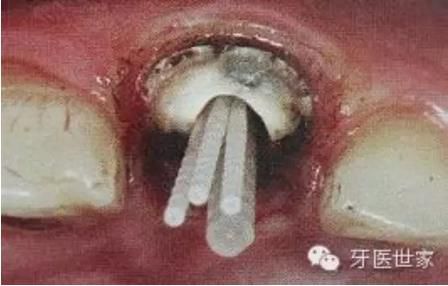

如果是后牙需要打多個纖維樁時要檢查是否互相妨礙以及就位順序等。

一般纖維樁使用數(shù)目要根據(jù)根管的粗細(xì)和牙體缺損范圍來設(shè)計,像牙膠尖根充一樣,在主尖周圍可以放置輔尖。

后牙一般按照牙體缺損范圍來設(shè)計,一般2到4個足夠了。